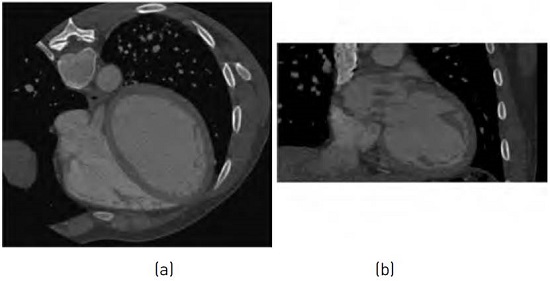

The second dataset corresponds with 4-D cardiac images sequences acquired using a MSCT scanner (Philips Brilliance 64 Host-10236). Each sequence consists of 10 volumes describing the heart anatomical information for a complete cardiac cycle. The resolution of each volumen is (512 × 512 × 324) voxels. The spacing between pixels in each slice is 0.429688 mm and the slice thickness is 0.400024 mm. The image volume is quantized to 12 bits per voxel. Therefore, a total of 1,270 3-D MSCT images from 126 patients is used in the experiment. Figure 3 shows a MSCT image.

Figure 4 shows the results obtained after performing the experiment associated with the analysis of the similarity criterion components for S1 strategy. In this figure, we can observe a slice of a 3-D MSCT image in each case and for the configuration of the neighborhood space with n = 4. Each image is associated with each case (main, residual1, residual2 or full).

Figure 5 shows the results obtained after performing the experiment associated with S2 strategy. Each image is associated with each case (main, residual1, residual2 or full). The neighborhood space used is n = 4.